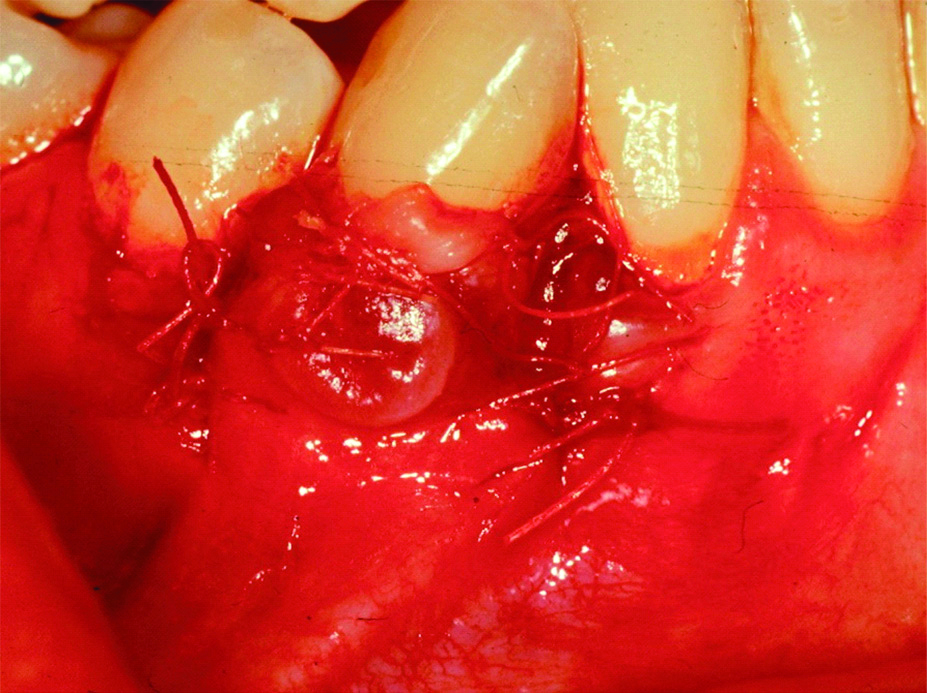

A 36-year-old female patient presented in to the periodontal clinic in 2002 with a complaint of long teeth and sensitivity in the lower right (#43) and left (#33) canines. The dental history revealed that the patient had a history of using an aggressive brushing technique, which caused generalised abrasion of the cervical region and resulted in the placement of a composite restoration to fill the abrasion area. Subsequently, gingival recession occurred in some areas, and root sensitivity reoccurred because of a leakage of these restorations. Clinical examination revealed the presence of gingival recessions of approximately 3-4 mm on teeth #33 and #43, with the presence of a composite restoration on the root surface [Table/Fig-1]. The recession defect was classified as Miller’s Class II, with 1 mm of a keratinised gingiva and no attached gingiva [1]. The probing depth ranged from 1 to 2 mm. The plaque index was 75%, with bleeding on probing of 55%. Phase I therapy consisted of scaling and root planing, with plaque control measures using a modified Stillman’s brushing technique and interdental flossing at home. The surgical phase consisted of removal of the old restoration and replaced with a new restoration which; was contoured to the crown only then, placement of a connective tissue graft, combined with a double-papilla flap. The patient agreed to the procedure and signed informed consent. Prior to soft tissue grafting, the composite restoration was removed from the root surface and contoured to the tooth crown only, and the root surface was smoothed with a finishing bur [Table/Fig-2]. The right side of the palate was used as a donor site, which was anaesthetised with one ampoule of lidocaine, while each recipient site received two ampoules. Blade #15 was used for incision placement and palatal tissue harvesting. Two oblique incisions of 3 mm long were placed on each side of the tooth, with two vertical incisions extended beyond the mucogingival junction. A partial thickness flap was utilised all the way long [Table/Fig-3]. A connective tissue graft of 13×5 mm, with 2-mm thickness after removal of adipose tissue, was harvested from the palate, and the donor site was secured with a 4-0 vicryl suture [Table/Fig-4]. The graft was divided in half, for teeth #33 and #43, respectively. The graft was then, sutured in place with a 5-0 vicryl suture using a simple interrupted technique; then, a double-papilla rotational flap was secured with 5-0 vicryl [Table/Fig-5]. No periodontal dressing was used. Postsurgical medication consisted of ibuprofen 400 mg/qid for four to seven days and rinsing with normal saline twice daily for seven days. The patient was instructed to eat soft food for seven days. Brushing of the surgical site was deferred for six weeks, and the patient was asked to use a cotton tip with mouthwash to clean the area twice daily. The sutures were removed after two weeks, and the healing was uneventful, with no complications [Table/Fig-6]. Since the patient had mild localised periodontitis, with a history of an aggressive brushing technique, she was placed on a maintenance recall every four months for suppurative periodontal therapy.

Flap design for a double-papilla flap.

Flap suturing for tooth #43.